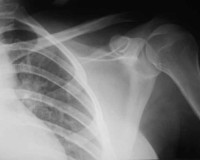

shoulder xray

FACTS: The Plaintiff went to the Defendant’s store to buy shoes. The Plaintiff slipped on a sale sign, which had fallen from its post, and fell down. The Plaintiff suffered sprains and strains and underwent knee and shoulder surgery.  Medical bills amounted to $ 115,309.29.